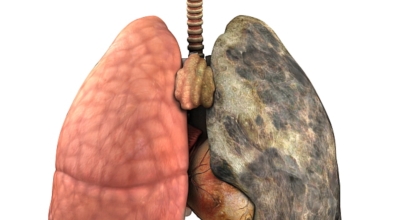

폐에 발생된 악성 종양을 말하며 오랜 기간 흡연해온 남성들에서 발병률이 높고 요즘 들어 가지가지 환경적인 요인의 영향과 간접흡연으로 흡연하지 않는 여성에서도 많이 발생하고 있답니다. 증상을 느껴 병원을 찾았을 때는 수술하기 늦은 경우가 많아 사망 확률이 매우 높은 암입니다. 폐 자체에서 생기거나 다른 장기에서 발생된 암이 폐로 전이되어 나타나기도 하고 특별한 초기 증상이 없는 경우가 많으며 암이 진행된 후에도 일반적인 감기 증상인 기침과 가래 외의 특이 증상이 나타나지않아 증상만으로는 진단이 쉽지 않아요.

폐암 검사는 X-ray를 통해서 검사하는데 , 크기가 작거나 구석에 위치한 경우 확인이 어려운 경우도 있습니다. 그리고 조직 검사를 통해서 정확한 진단을 하게 돼요. 폐암이 발견되면 종양의 크기나 전이 여부 , 위치에 따라서 수술 여부를 결정하게 돼요.